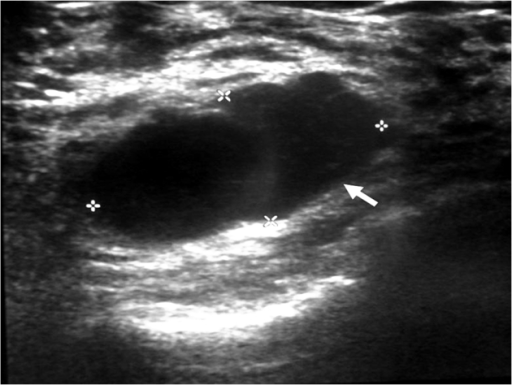

Ultrasound Examination Of The Right Breast Showing A We | Open-i

breast ultrasound right hypoechoic mass enhancement lobulated showing circumscribed well examination margins internal echogenicity open acoustic figure posterior shadowing lesions

What are the symptoms of metastatic breast cancer?. Breast ultrasound right hypoechoic mass enhancement lobulated showing circumscribed well examination margins internal echogenicity open acoustic figure posterior shadowing lesions. What is a clear margin in breast conserving cancer surgery?